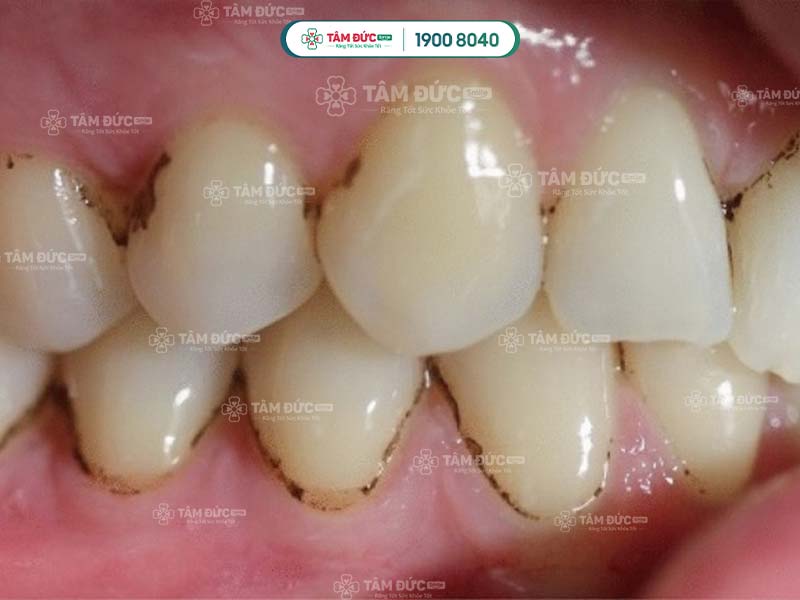

Tại đây, bác sĩ sẽ dùng các dụng cụ chuyên dụng để làm sạch cao răng. Lấy cao răng tại nha khoa được thực hiện bằng công nghệ sóng siêu âm hiện đại, đảm bảo hiệu quả và an toàn. Sóng siêu âm tác động lên cao răng mà không gây xâm lấn, bảo toàn các tổ chức quanh chân răng ở mức tối đa.

Lấy cao răng bị đen bằng sóng siêu âm là kỹ thuật mới nhất được áp dụng tại nha khoa uy tín. Quý khách sẽ không cảm thấy bị đau và chỉ mất khoảng 10-15 phút thực hiện.

Lấy cao răng bị đen an toàn không đau tại nha khoa Tâm Đức Smile